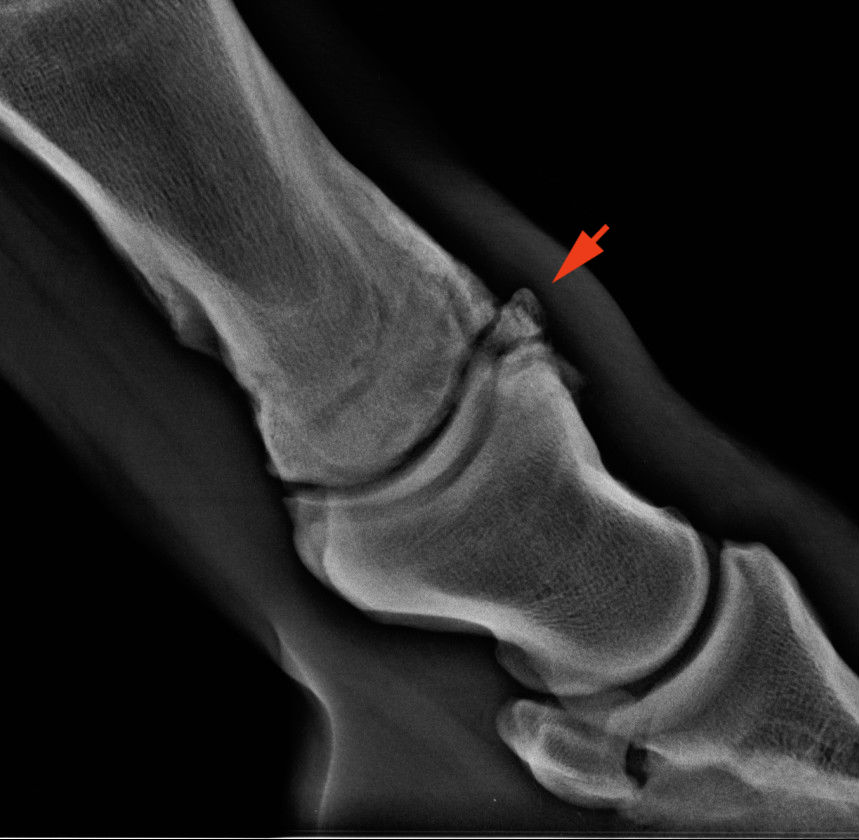

„Chip” törés a pártaízületben

Az alaki elváltozások közül elsősorban a törésekre és repedésekre, valamint a „chip” törésekre (OCD) kell gondolni elsősorban. Fontos tudni, hogy a repedések sokszor nem látszanak azonnal a felvételeken, hiszen a repedés mellett a csontok olyan szorosan egymás mellett fekhetnek, hogy nincs rés köztük. De 10-20 nap alatt a csontállomány oldódni kezd és a repedés láthatóvá válik. A törések diagnosztikájához a röntgen nem mindig elegendő, ilyenkor CT vizsgálat vagy a szcintigráfia is segíthetnek a pontos kép kialakításában.